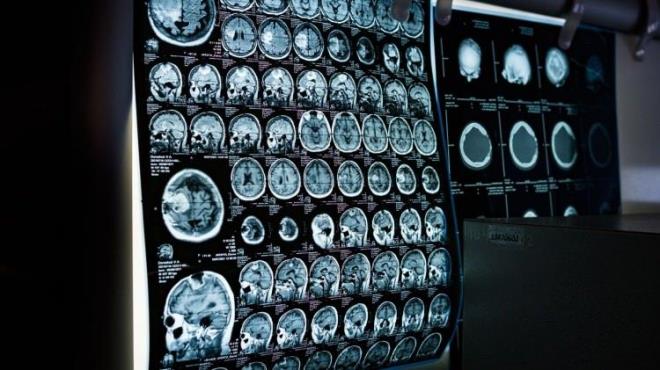

Japonya'da bir bilim insanı, beyin görüntüleme yöntemleri ve yapay zekadan yararlanarak insanların zihninde canlandırdığı görüntüleri sözcüklere dökebilen "zihin betimleme" adlı yeni bir yöntem geliştirdi. Science Advances dergisinde yayımlanan çalışma, dünya çapında geniş yankı uyandırdı.

Japonya'da yer alan Nippon Telegraph ve Telephone telekomünikasyon şirketinin İletişim Bilimleri Laboratuvarı'nda çalışan araştırmacı Horikawa Tomoyasu, beyin taramaları ve yapay zeka kullanarak insanların zihnindeki görsel imgeleri doğru ve detaylı cümlelere dönüştüren bir yöntem geliştirdi.